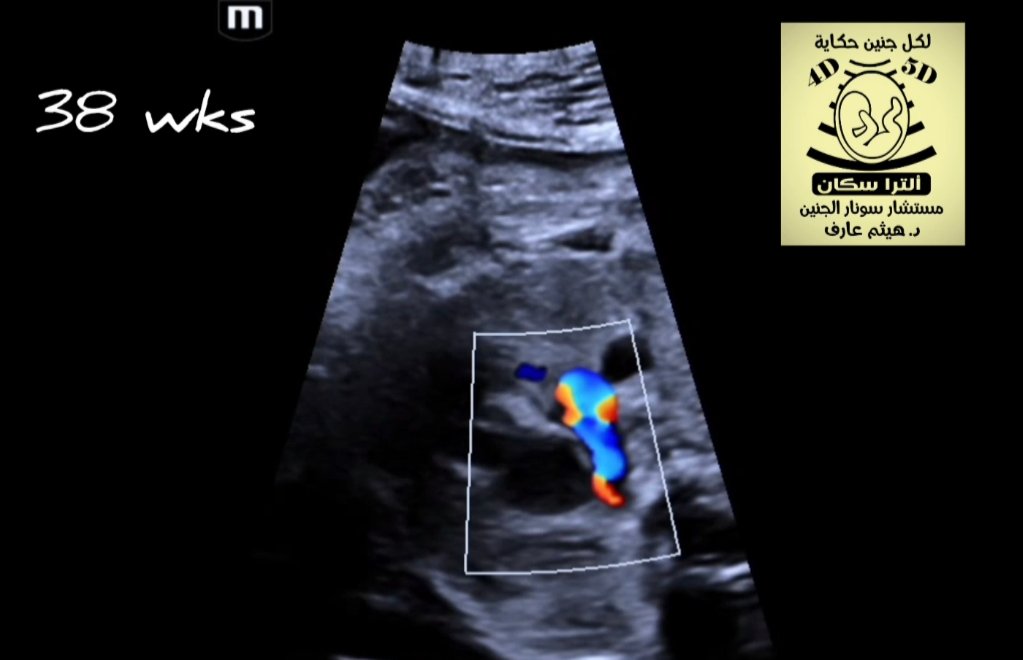

Premature constriction of ductus arteriosus

Premature constriction of ductus arteriosus Prominent right ventricle s.ulging to left ventricle and decreased flow in right side in comparison to left ventricle No flow in ductusDilated proximal pulmonary arteryReversal in aortaAt the end of the clip occasional reversed Flow in DVImmediate delivery of baby recommended Now baby is fine! Premature constriction of ductus arteriosus Prominent right ventricle slightly bulging to left ventricle and decreased flow in right side in comparison to left ventricle No flow in ductusDilated proximal pulmonary arteryReversal in aortaAt the end of the clip occasional reversed Flow in DVImmediate delivery of baby recommended Now baby is fine!